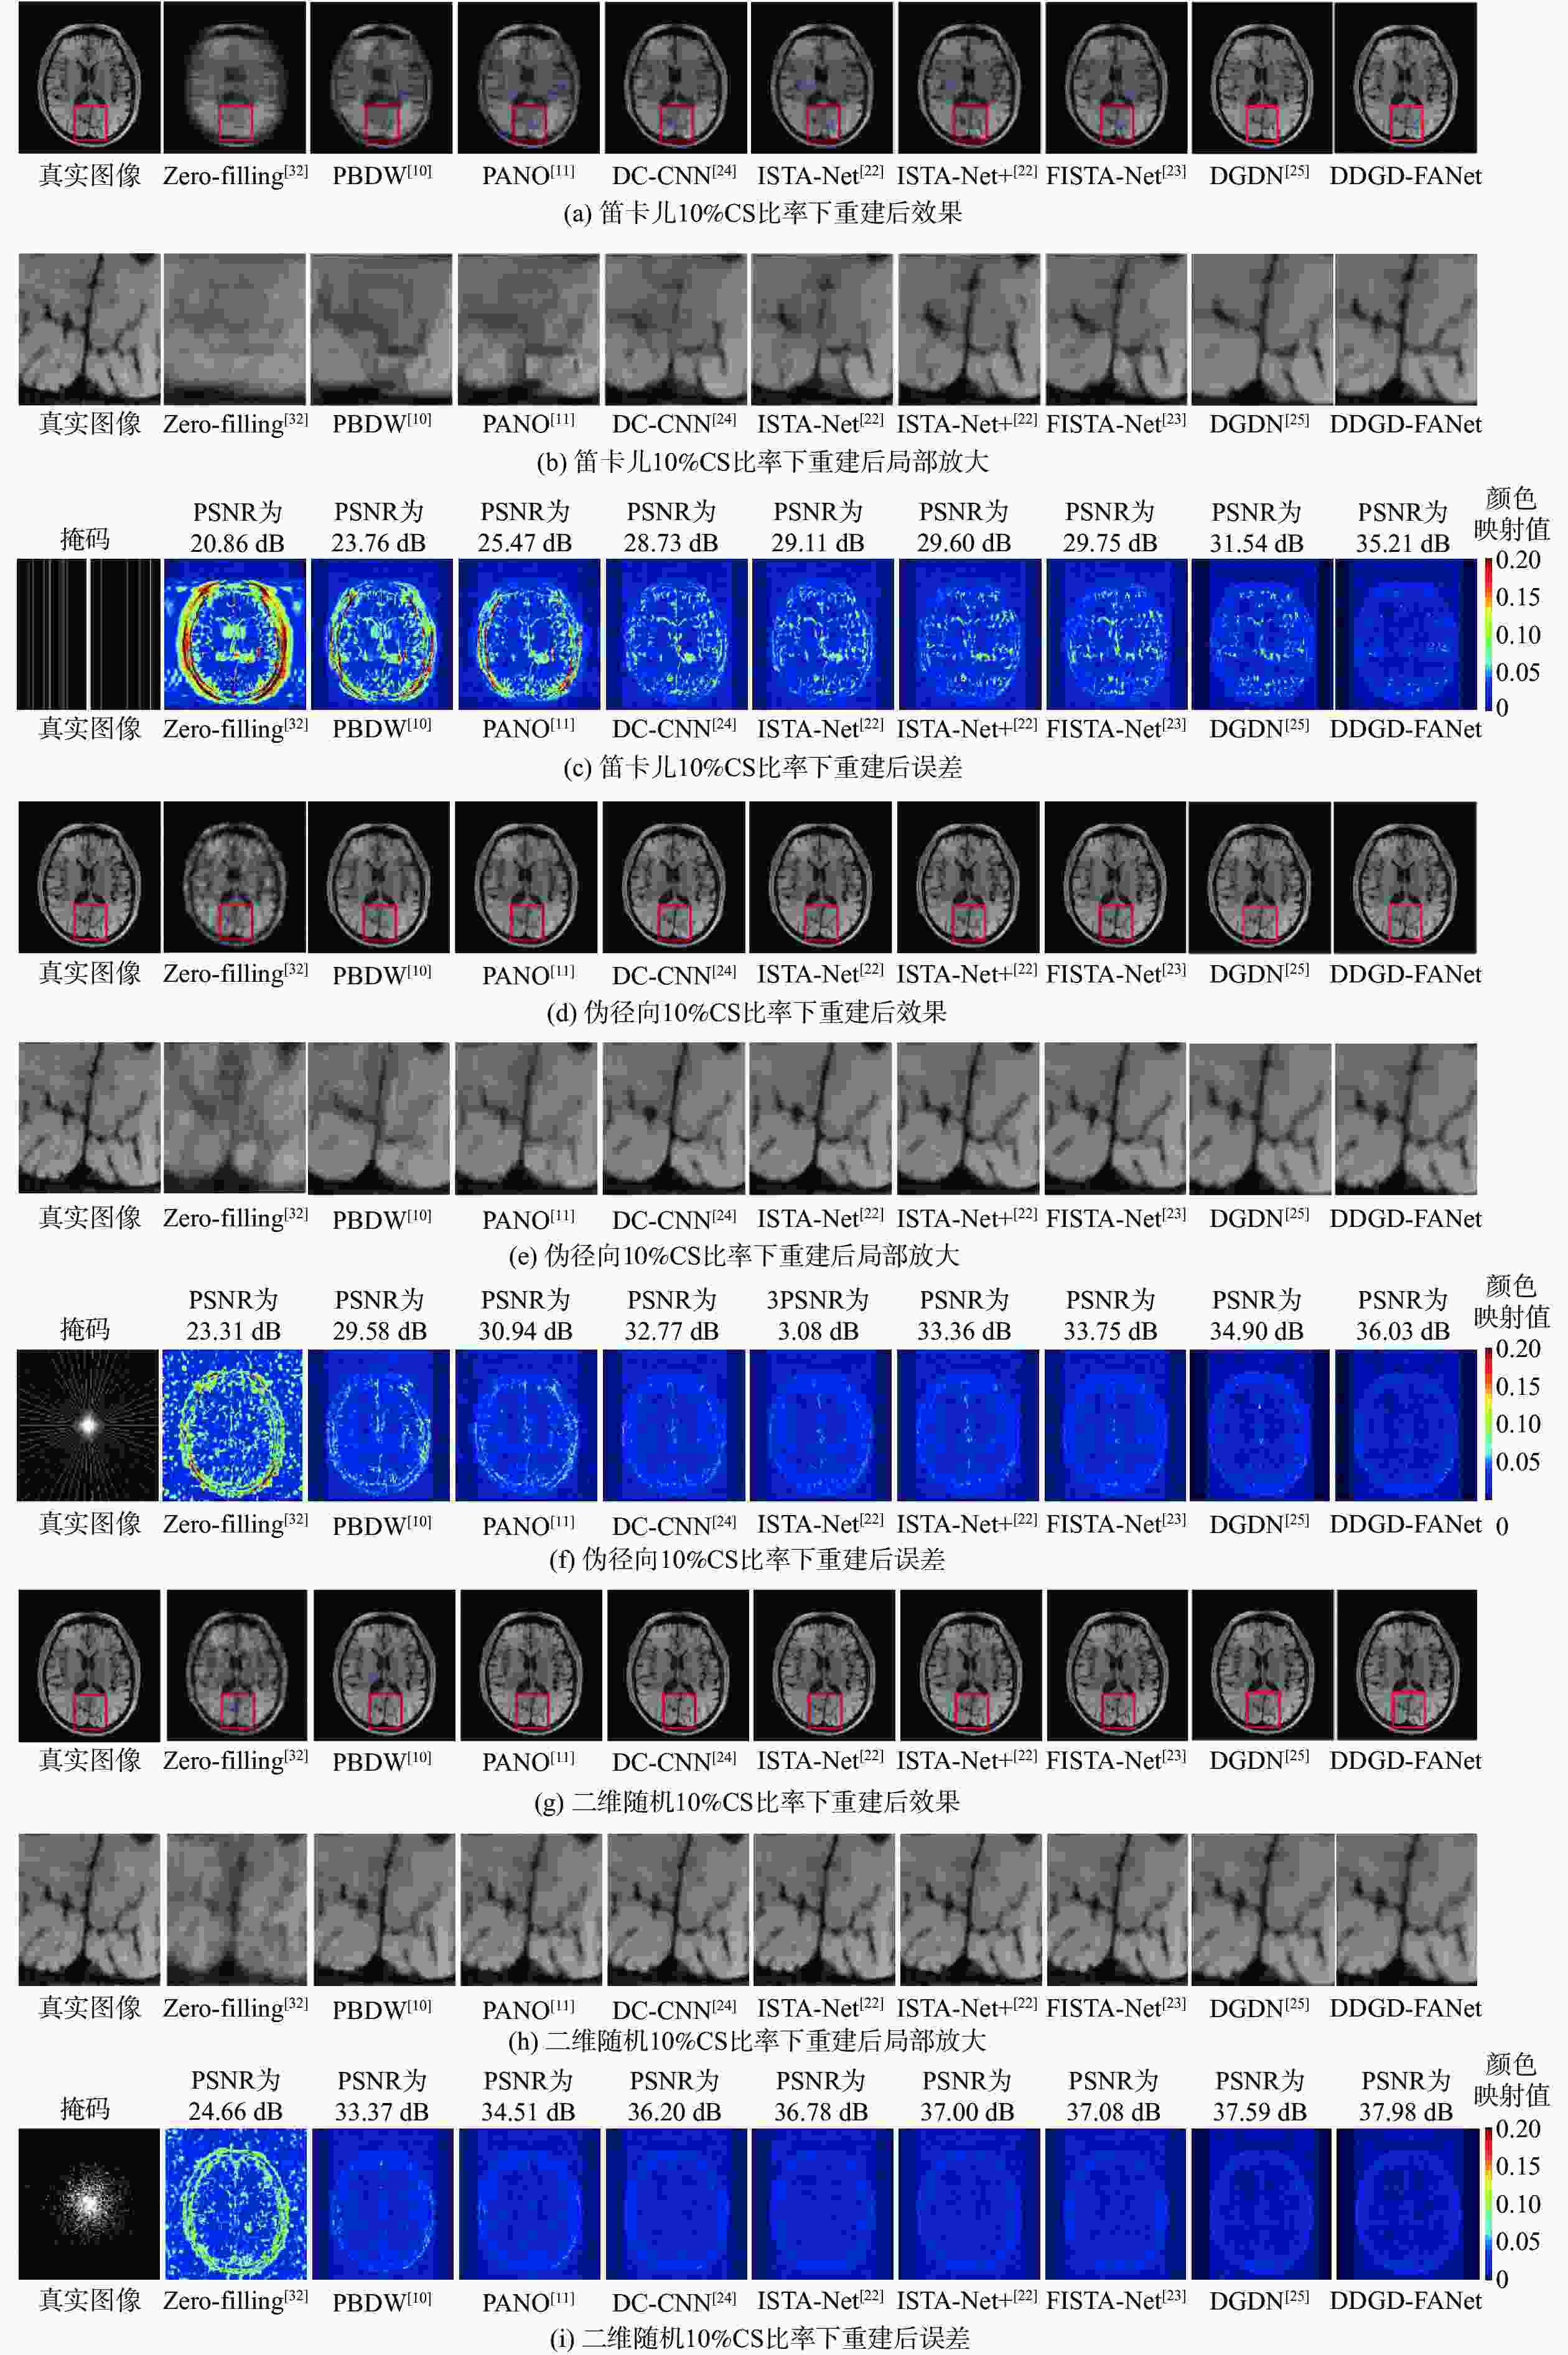

虽然现有基于深度学习的压缩感知磁共振成像(CS-MRI)方法已经取得了较好的效果,但这些方法的可解释性仍然面临挑战,并且从理论分析到网络设计的过渡并不够自然。为解决上述问题,提出深度双域几何蒸馏特征自适应网络(DDGD-FANet)。该深度展开网络将磁共振成像重建优化问题迭代展开成3个子部分:数据一致性模块、双域几何蒸馏模块和自适应网络模块,不仅可以补偿重建图像丢失的上下文信息,恢复更多的纹理细节,还可以去除全局伪影,进一步提高重建效果。在公开数据集使用3种不同的采样模式进行实验,结果表明:DDGD-FANet在3种采样模式下均取得了更高的峰值信噪比和结构相似性指数,在笛卡儿10%压缩感知(CS)比率下,峰值信噪比较迭代收缩阈值算法(ISTA-Net+)、快速ISTA(FISTA)-Net和DGDN模型分别提高了5.01 dB、4.81 dB和3.34 dB。

Abstract:Although the existing compressed sensing-magnetic resonance imaging (CS-MRI) methods based on deep learning have achieved good results, the interpretability of these methods still faces challenges, and the transition from theoretical analysis to network design is not natural enough. In order to solve the above problems, this paper proposed a deep dual-domain geometry distillation feature adaptive network (DDGD-FANet). The deep unfolding network iteratively expanded the MRI reconstruction optimization problem into three sub-modules: data consistency module, dual-domain geometry distillation module, and adaptive network module. It could compensate for the lost context information of the reconstructed image, restore more texture details, remove global artifacts, and further improve the reconstruction effect. Three different sampling modes were used in the public dataset. The results show that DDGD-FANet achieves a higher peak signal-to-noise ratio and structural similarity index in all three sampling modes. At the Cartesian 10% compressed sensing(CS )ratio, the peak signal-to-noise ratio is increased by 5.01 dB, 4.81 dB, and 3.34 dB, respectively, higher than that of iterative shrinkage-thresholding algorithm (ISTA)-Net +, fast ISTA (FISTA)-Net, and DGDN models.

掩码类型 方法 PSNR/dB SSIM CS比率为10% CS比率为20% CS比率为30% CS比率为10% CS比率为20% CS比率为30% Zero-filling[32] 23.84 26.40 31.14 0.574 3 0.661 1 0.786 5 PBDW[10] 26.82 32.41 35.05 0.735 5 0.866 0 0.911 6 PANO[11] 28.98 34.62 36.75 0.789 7 0.893 3 0.922 2 DC-CNN[24] 30.04 35.75 38.48 0.823 5 0.920 5 0.949 3 笛卡儿 ISTA-Net[22] 30.28 36.58 39.17 0.825 6 0.933 4 0.956 8 ISTA-Net+[22] 30.86 37.03 39.63 0.845 5 0.935 5 0.959 7 FISTA-Net[23] 31.06 37.29 39.86 0.844 4 0.939 6 0.960 7 DGDN[25] 32.53 38.31 40.61 0.886 3 0.949 9 0.965 6 DDGD-FANet 35.87 39.55 41.41 0.932 0 0.959 3 0.970 1 表 2 不同CS比率伪径向和二维随机采样模式下大脑数据集建效果对比

方法PSNR/dB CS比率为10% CS比率为20% CS比率为30% 伪径向 Zero-filling[32] 26.64 30.32 32.93 PBDW[10] 32.48 36.53 38.95 PANO[11] 33.61 37.01 39.29 DC-CNN[24] 34.32 38.43 40.75 ISTA-Net[22] 34.70 38.74 41.01 ISTA-Net+[22] 34.83 38.75 41.00 FISTA-Net[23] 35.10 39.05 41.19 DGDN[25] 35.91 39.33 41.34 DDGD-FANet 37.08 39.67 41.54 二维随机 Zero-filling[32] 27.71 29.36 31.13 PBDW[10] 35.68 38.49 40.83 PANO[11] 36.60 39.57 42.03 DC-CNN[24] 37.65 40.81 43.40 ISTA-Net[22] 38.22 41.40 43.97 ISTA-Net+[22] 38.41 41.66 44.20 FISTA-Net[23] 38.36 41.75 44.29 DGDN[25] 38.85 41.91 44.38 DDGD-FANet 39.25 42.13 44.53 表 3 本文模型消融实验结果